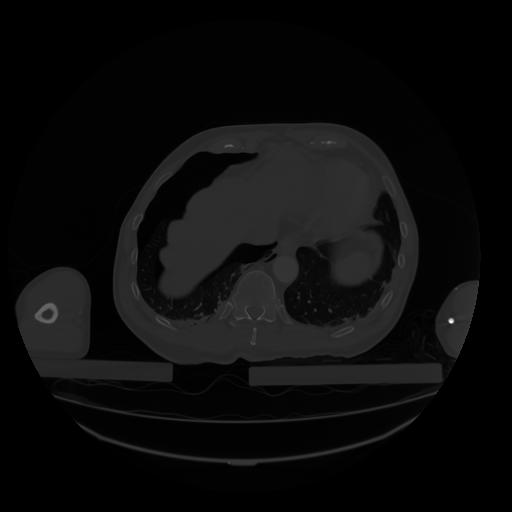

28 CUERPO,CE,Vol,2.0,CUERPO,,